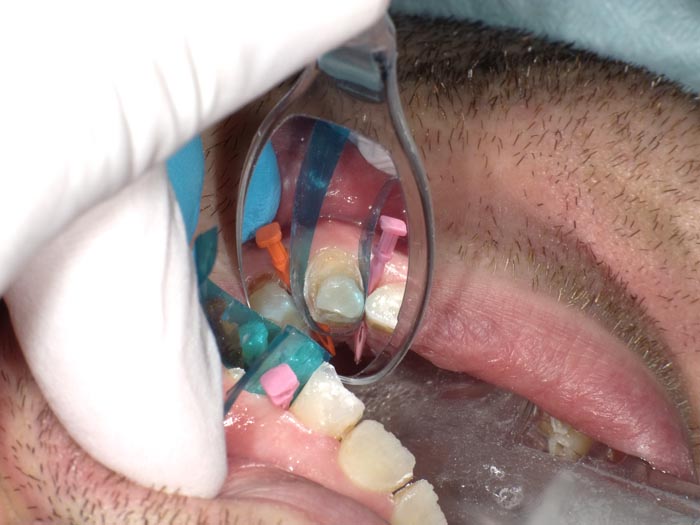

Case 4

A 54-year-old patient presented for replacement of failing amalgam on #12.

• Figure 16

• Figure 17

• Figure 18

• Figure 19A

• Figure 19B

• Figure 20A

• Figure 20B

• Figure 21

• Figure 22